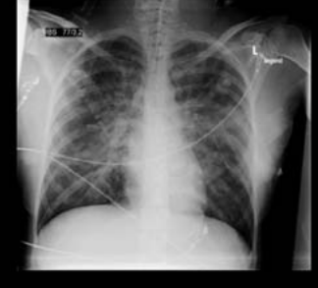

Die Fruchtwasserembolie ist eine seltene, aber akut lebensbedrohliche Komplikation in der Schwangerschaft, unter der Geburt oder postpartal. Fruchtwasser tritt über venöse Gefässe in den mütterlichen Kreislauf ein und löst eine anaphylaktoide Reaktion aus mit Entwicklung einer kardiopulmonalen Dekompensation und disseminierten intravasalen Koagulopathie. Die mütterliche Mortalität ist mit 30–90% relativ hoch. Häufig sind auch hypoxiebedingte irreversible neurologische Defizite. Im Mai dieses Jahres...